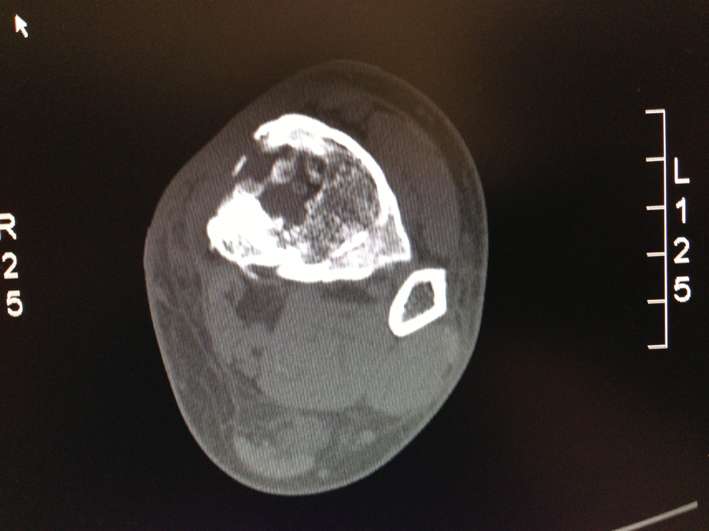

Lo stato dell'osso, in quella data era cosi, come si vede da questo fotogramma della TAC:

La parte nera a ore 11 è l'infezione: ciò vuol dire che dentro all'osso ho una zona, ovale grande come due acini d'uva, infetta e che sto in piedi per miracolo e per quella corteccia appuntita al lato opposto che si è formata con la calcificazione. La piastra mi è stata tolta appunto per questa corteccia.